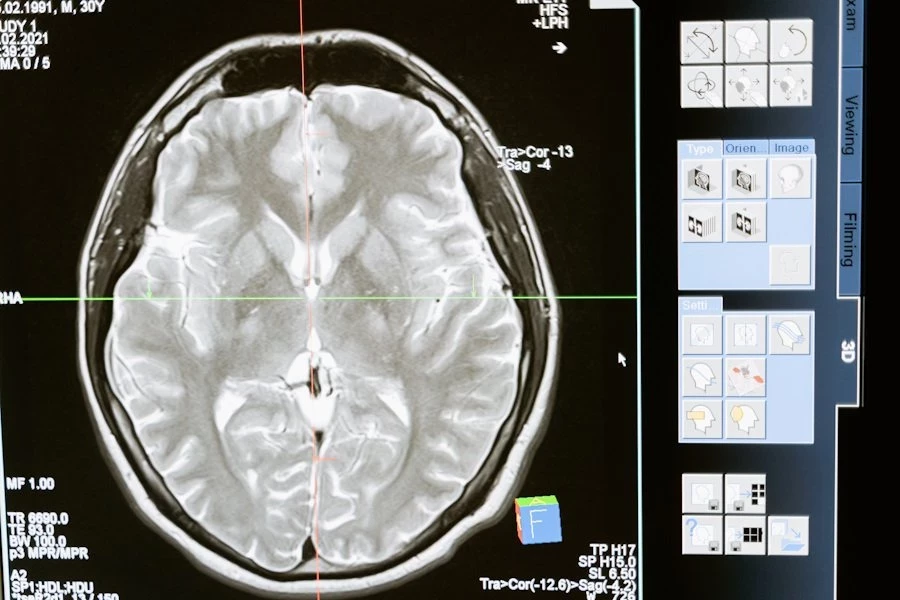

Ученые из University of Texas at Austin  разработали инновационные текучие чернила для электроэнцефалографии (ЭЭГ). Этот метод исследования активности мозга стал не только точнее, но и комфортнее для пациентов.

Сейчас стандартный процесс ЭЭГ требует прикрепления десятков электродов к коже головы. Это не только занимает много времени, но и вызывает дискомфорт, особенно при длительных исследованиях. Новая технология решает эти проблемы с помощью электронных татуировок (e-tattoos).